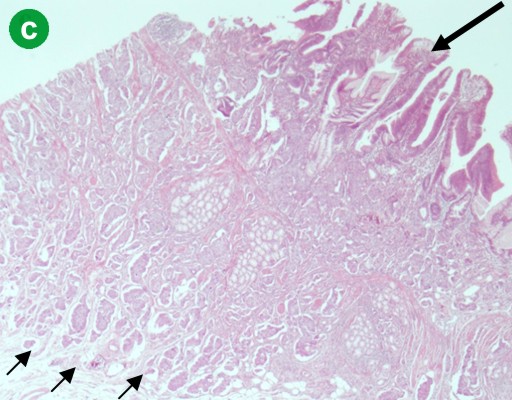

A pancreaticoduodenectomy was performed, showing an exophytic duodenal tumor invading the ampulla of Vater, measuring 4.5x5.0 centimeters. At the center of this tumor, a well delineated red-brown nodule measuring 12 mm was observed (Figure 1b). Microscopic examination identified two distinct tumor cell populations. The first one corresponded to an exocrine high grade tubulo-villous adenoma largely extending onto the external part of the ampulla and to the duodenal mucosa (Figure 2a). An area of well-differentiated adenocarcinoma was identified inside the adenoma, measuring 6 mm, infiltrating the duodenal submucosa but sparing the muscularis propria (Figure 2b). The second tumor cell population was of endocrine type. It formed a well-delineated central nodule of 1 cm, sharply demarcated from the exocrine component (Figure 2c). It was composed of cords or acini of well-differentiated endocrine cells combined with psammoma bodies (Figure 2d). Endocrine cells contained regular nuclei, and granular and eosinophilic cytoplasm. Mitotic activity was low (less than 2 mitoses per 10 high-power fields). Immunohistochemical analysis demonstrated positive and diffuse staining of the endocrine component with antibodies directed against the neuroendocrine markers synaptophysin and CD56 and with anti-somatostatin antibody (Figure 2e). Chromogranin A was negative. The proliferation index, evaluated using MIB-1 antibody according to the TNM classification [1] was calculated at 2%. The main pancreatic duct was invaded by the adenomatous high grade component, but the secondary ducts and biliary duct did not display any dysplasia or malignant features. The infiltrating tumors did not extend into the pancreatic parenchyma. Lymph node dissection revealed 6 metastatic nodes: 3 were metastatic from the adenocarcinoma component and 3 from the endocrine carcinoma (Figure 2f).

Figure 2. a. The high grade tubulo-villous adenoma extending to the duodenal mucosa (H&E staining, x200). b. An area of well differentiated adenocarcinoma infiltrating the duodenal submucosa (H&E, x400). c. The endocrine component (small arrows) is located under the exocrine high grade adenoma (large arrow) (H&E, x100). d. The endocrine component is well differentiated and contains psammoma bodies (arrows) (H&E, x400). e. Endocrine tumor cells abundantly and diffusely expressing somatostatin (immunostaining with somatostatin antibody, counterstained with hematoxylin; x 200). f. Metastatic lymph nodes are present, either from the exocrine (left) or the endocrine (right) component (H&E, x100). |